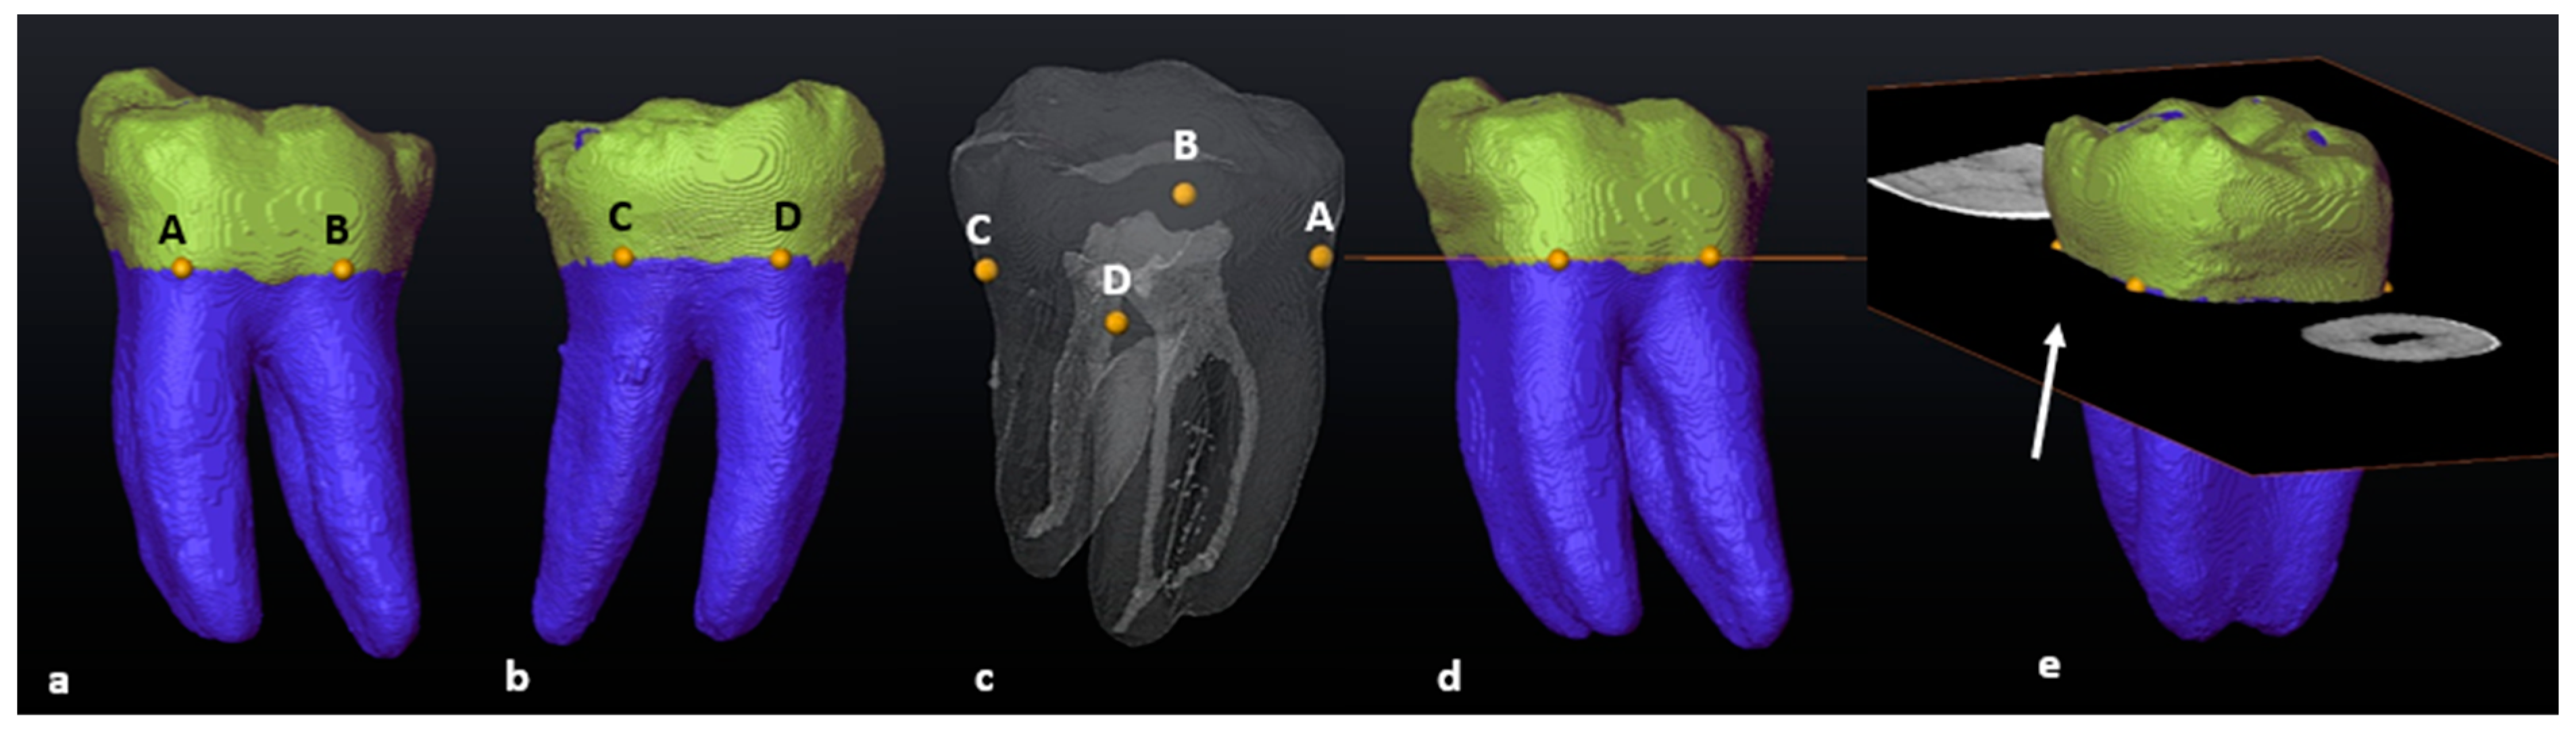

2.5. Scan Alignment

2.6. Segmentation and Landmark Identification

3.1. Mandibular First Molars: Two Rooted